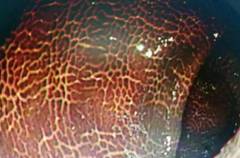

肠镜可见,其结肠已大范围发黑,黑色素呈条纹状、斑片状沉着在结肠黏膜上,仿佛"豹纹",又像蛇皮,被确诊为结肠黑变病。见下图:

结肠黑变病(MC)是结肠黏膜固有层中巨噬细胞内色素聚集的一种黏膜色素沉着性为特征的非炎性、良性可逆性病变,常与息肉、肿瘤伴发,也有观点认为有一定的癌变几率。